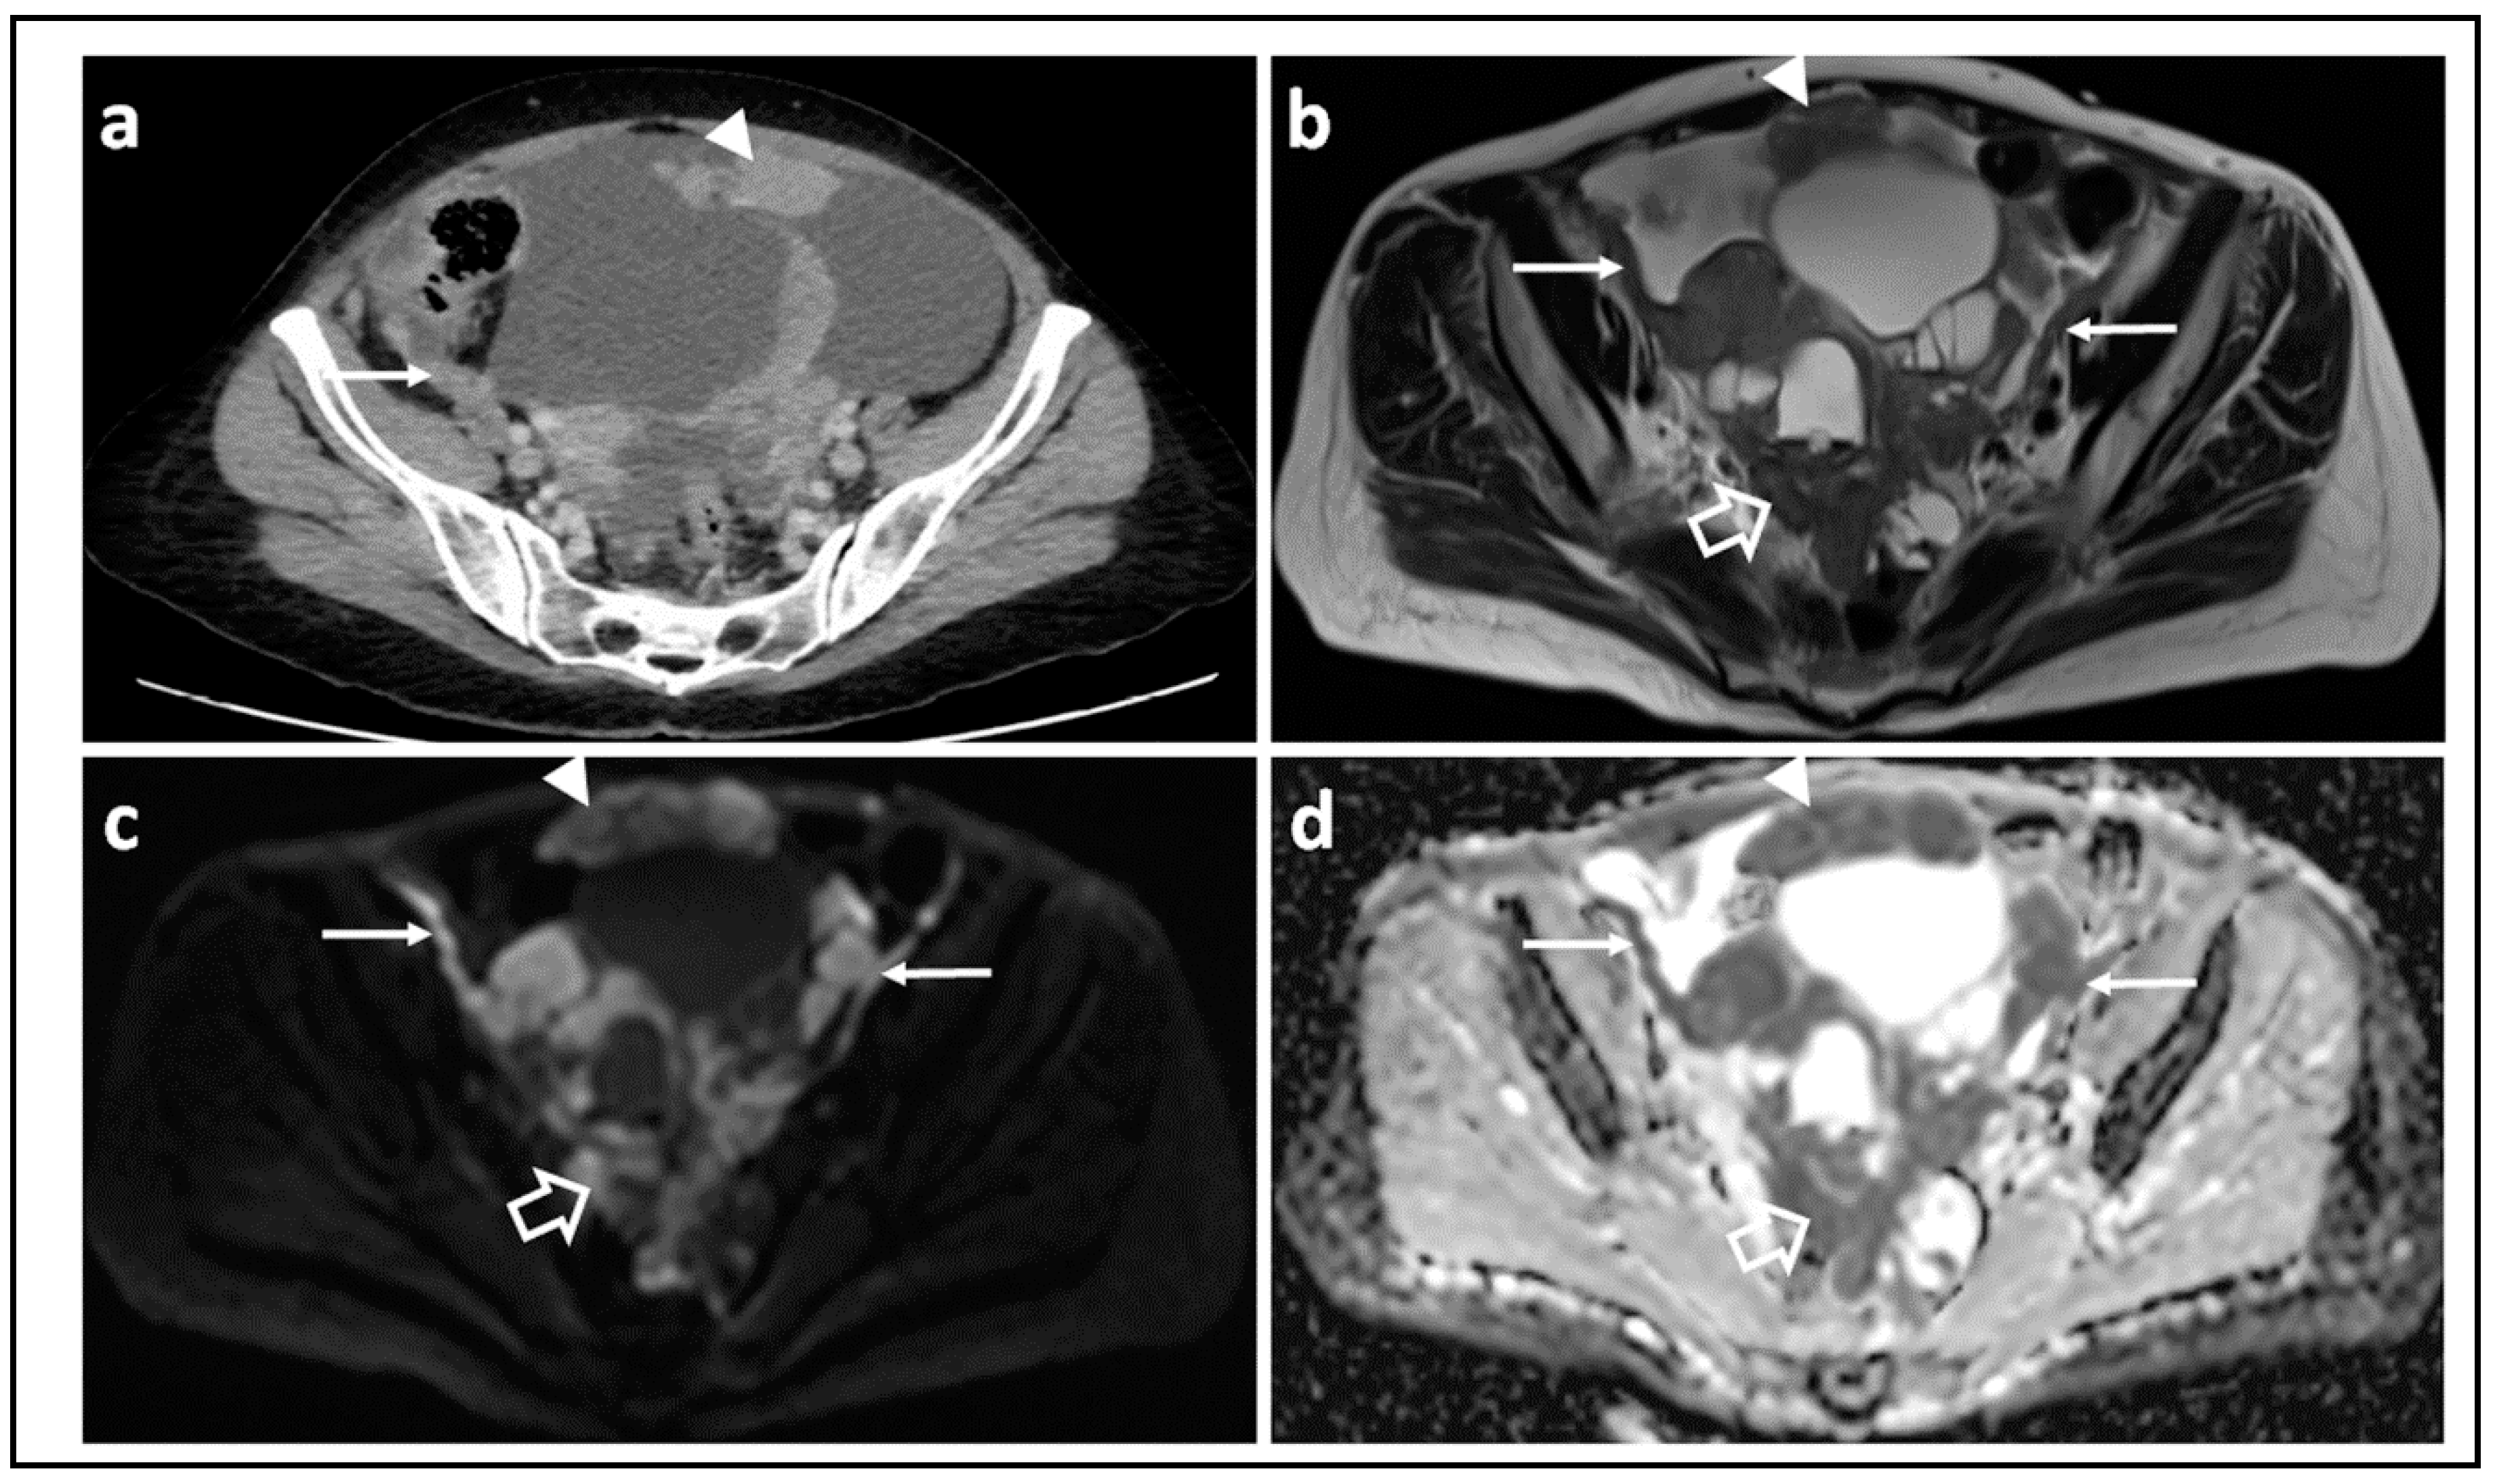

Figure 3.

Assessing disease extent using CT versus MRI: CT scan (a) T2-W image (b) and corresponding b = 1050 s/mm2 DW-MRI (c) and ADC map (d) through the mid-pelvis in a patient with high grade serous ovarian cancer before treatment. The peritoneal (arrow) and omental disease (arrowhead) is evident in (a), but the extent of peritoneal and serosal disease encasing the sigmoid colon is more striking on MRI (open arrows) where it appears as high signal within the pelvis in (c). Marked diffusion restriction is confirmed in (d).